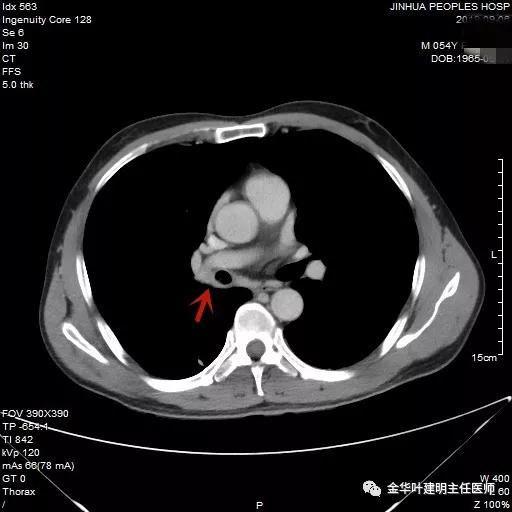

上面各图示肿瘤位于肺门部,堵塞下叶及中间支气管

我们仔细看了增强CT,纵隔未见确切疑似转移的肿大淋巴结,这样的情况下,是不是再次气管镜活检,还是直接可以手术?当然从原则上来讲,应该再重新纤支镜检查,再活检以取得病理确诊后,再行手术。但个人以为,从影像及气管镜所见来讲,临床诊断已经可以确定为肺癌,而且中央型的以鳞癌为多见,当然也有的会是小细胞癌,不过小细胞癌一般很早就会有纵隔淋巴结转移,如果患者及家属理解,我认为从减少痛苦、节约经费、节省时间等方面考虑,直接手术也基本不会错的。当然所有的利弊与可能都要如实与患者及家属沟通,并征求他们的意见,最终李某及家属选择不再重新纤支镜检查与活检,要求直接手术。